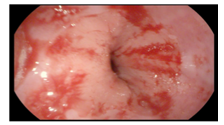

影像学检查:2021.02.20腹部CT:胃窦癌(T3/4期)幽门上下多发小淋巴结。

图1 腹部CT

增强CT检查(2021.4.14):胃角、胃窦小弯侧局部胃壁增厚,考虑胃癌(T3N0M0)。

增强CT检查(2021.6.9):胃腔充盈良好,胃壁未见局限性增厚,胃窦部胃壁未见异常强化(见图5)。

图5 增强CT